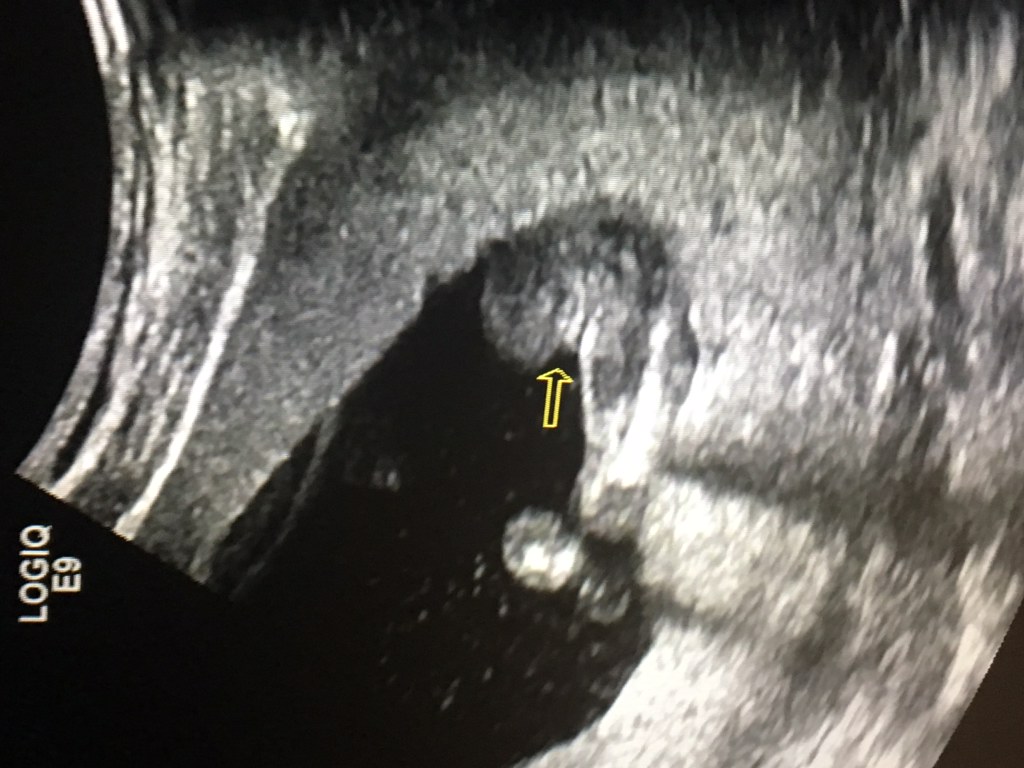

Attachment 37644Posting for a friend who is 13 weeks and six days by ultrasound. What are your thoughts?!

Boy

Looks like a boy

Boy [emoji170]